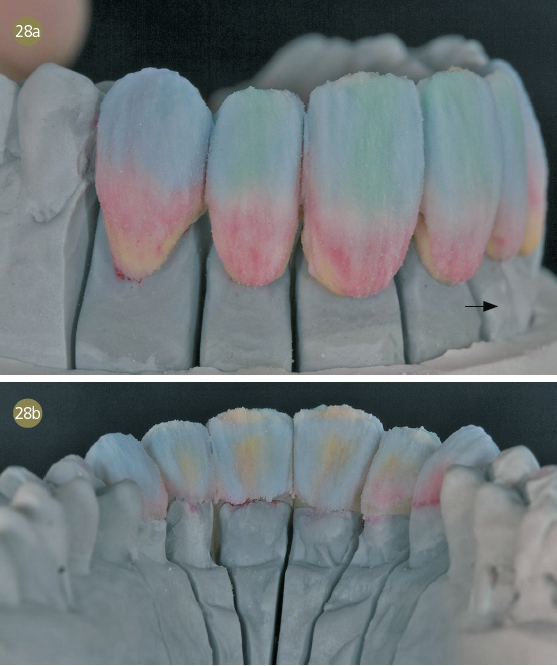

Wax-up

Es half der Patientin sehr, das Wax-up auf dem Gipsmodell anzuschauen. Gute Erfahrungen, in bestimmten Fällen ein Waxup zu fertigen und es mit dem Behandler zusammen mit den Patienten zu besprechen, machen wir immer wieder. Gerade bei Patienten mit einer hohen Erwartung ist es essenziell, sie in die Behandlungsplanung mit einzubeziehen und laienverständlich vorzugehen. So haben wir auch der Patientin genau dargelegt, wie wir zu ihrer neuen Zahnform kamen. Mithilfe des „Digital Smile Design“ nach Dr. Christian Coachman zeigten wir ihr unsere Vorstellung der bestmöglichen Versorgung. Dies ist für mich unerlässlich in der täglichen Arbeit geworden. Auch die Patienten lieben diese Art der Kommunikation zusätzlich zum Wax-up auf dem Gipsmodell.